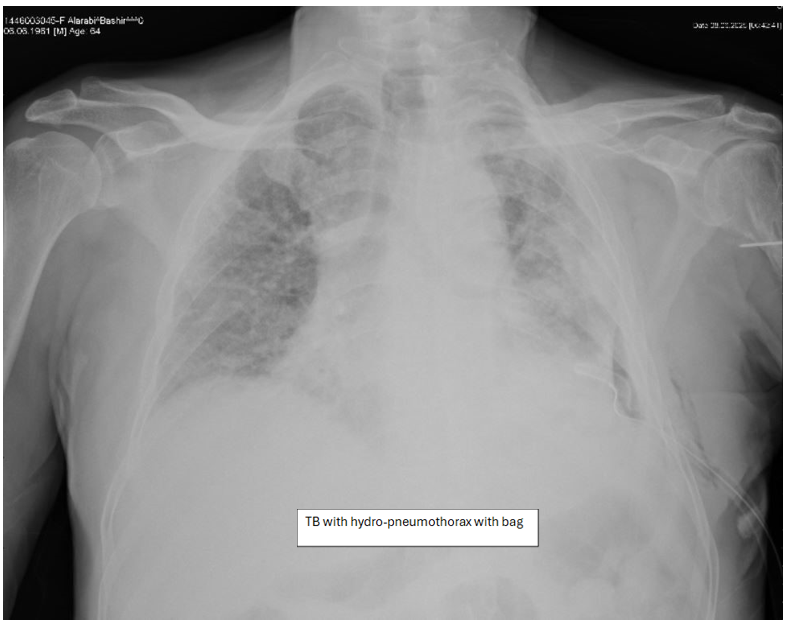

• Patients with tuberculosis either effusion or pneumothorax once clinical stable and cleared by infectious disease were safely discharged with bag and shows improvement on follow-up.

Figure 3